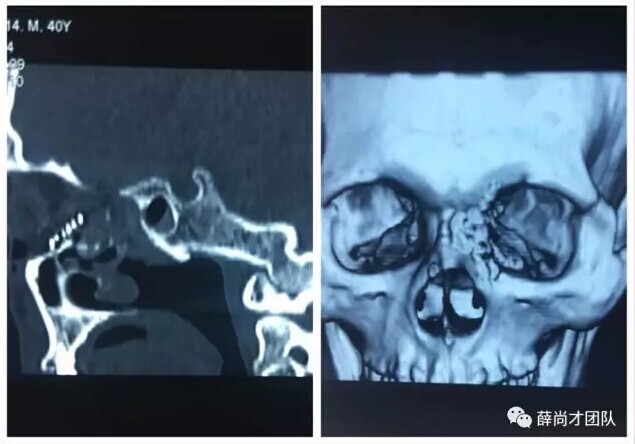

甘肃省二院眼科开展经眼眶视神经减压术使许多外伤失明的患者重见光明------2017-04-28 发布时间:2017-04-28 来源: 作者:

本文转自:薛尚才团队